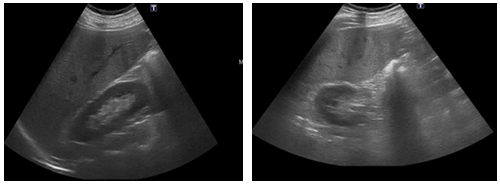

A 49-year-old male patient presents with a clinical picture of 11days of vomiting and diarrhea accompanied by abdominal pain, fever and jaundice during the last two days. Clinical history is positive for systemic hypertension, obesity and smoking. Physical exam showed tachycardia, jaundice and tenderness in the upper abdomen. Lab works showed: no leukocytosis, neutrophilia of 92%, liver enzymes of 115mU/ml and 179 mU/ml. Alkaline phosphatase of 129U/I, total bilirubin levels of 5.2mg/dl, Direct bilirubin of 3.3mg/dl, indirect bilirubin of 1.9 mg/dl, HDL of 250U/l, Amylase of 289U/dl, Lipase of 1900U/L, C-reactive protein of 24mg/dl, Electrolytes, renal function and coagulation were all normal. Hepatobiliary ultrasound showed a collapsed gallbladder (Figure 1). Bile system MRI showed thickened gallbladder wall, no gallstones, normal bile duct, dilated superior mesenteric vein with flow defect suggesting thrombosis (Figure 2). Contrast abdominal CT showed peri-appendicular inflammatory changes including a single fluid collection of 17x16mm, peripancreatic fluid and SMV flow defect-opacification indicating thrombosis (Figure 3). Normal Endoscopic ultrasound (Figure 4). The patient had findings suggesting systemic inflammatory response syndrome however in the absence of peritoneal irritation and ongoing pancreatitis, a conservative antibiotic treatment was chosen with ampicillin tazobactam, anticoagulation therapy with LMW heparin for 10days. The patient is discharged with a 21day antibiotic and 6month anticoagulation therapy. Appendectomy was programmed thereafter and the patient had full recovery.

Figure 1 Diffuse hepatic parenchymal echogenicity alteration, non-dilated bile ducts and collapsed gallbladder. Normal pancreas and spleen without free peritoneal fluid.